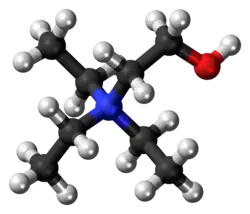

Triethylcholine

| Formula | C8H20NO |

| Molar mass | 146.254 g·mol−1 |

| 3D model (JSmol) | |

Triethylcholine is a drug which mimics choline, and causes failure of cholinergic transmission by interfering with synthesis of acetylcholine in nerve endings.[1]